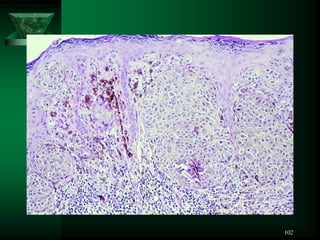

NEVUS

102